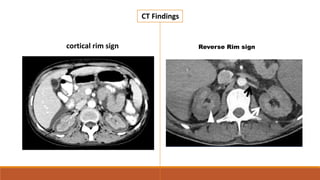

cortical rim sign Reverse Rim sign

CT Findings cortical rimsign Reverse Rim sign

• #24 Axial post-contrast CT scan (corticomedullary phase) absence of contrast enhancement in the cortex and relatively hyperdense medulla and subcapsular cortex, the characteristic ‘cortical rim sign’ Preserved enhancement of thin rim of subcapsular cortical tissue due to separate capsular blood supply a bilateral hypoattenuating renal cortex compared with intact medullary enhancement, which is called “reverse rim sign” (white arrowhead), and In contrast enhanced ct In arterial phase the ct scan shows senhancement of inter lobular and arcuate arteries adjacent to the non enchancing cortex. In the portovenous phase the CT shows enchnacement of the renal medulla with a hypoantttenuating non enchanging cortex ,this is called the reverse rim sign